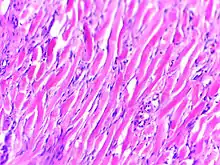

علم الأمراض

من الناحية النسيجية، الجُدرة هي أورام متليفة تتميز بمجموعة من الخلايا الليفية غير النمطية مع ترسب مفرط لمكونات المصفوفة خارج الخلية خاصةً الكولاجين، والفبرونيكتين، والإيلاستين، والبروتيوغليكان. وتقدم الجدرة تحديًا علاجيًا يجب معالجته، حيث يمكن أن تسبب هذه الآفات ألمًا كبيرًا وحكة وتشويهًا جسديًا. وقد لا تتحسن في المظهر بمرور الوقت ويمكن أن تحد من القدرة على الحركة إذا كانت موجودة على مفصل.